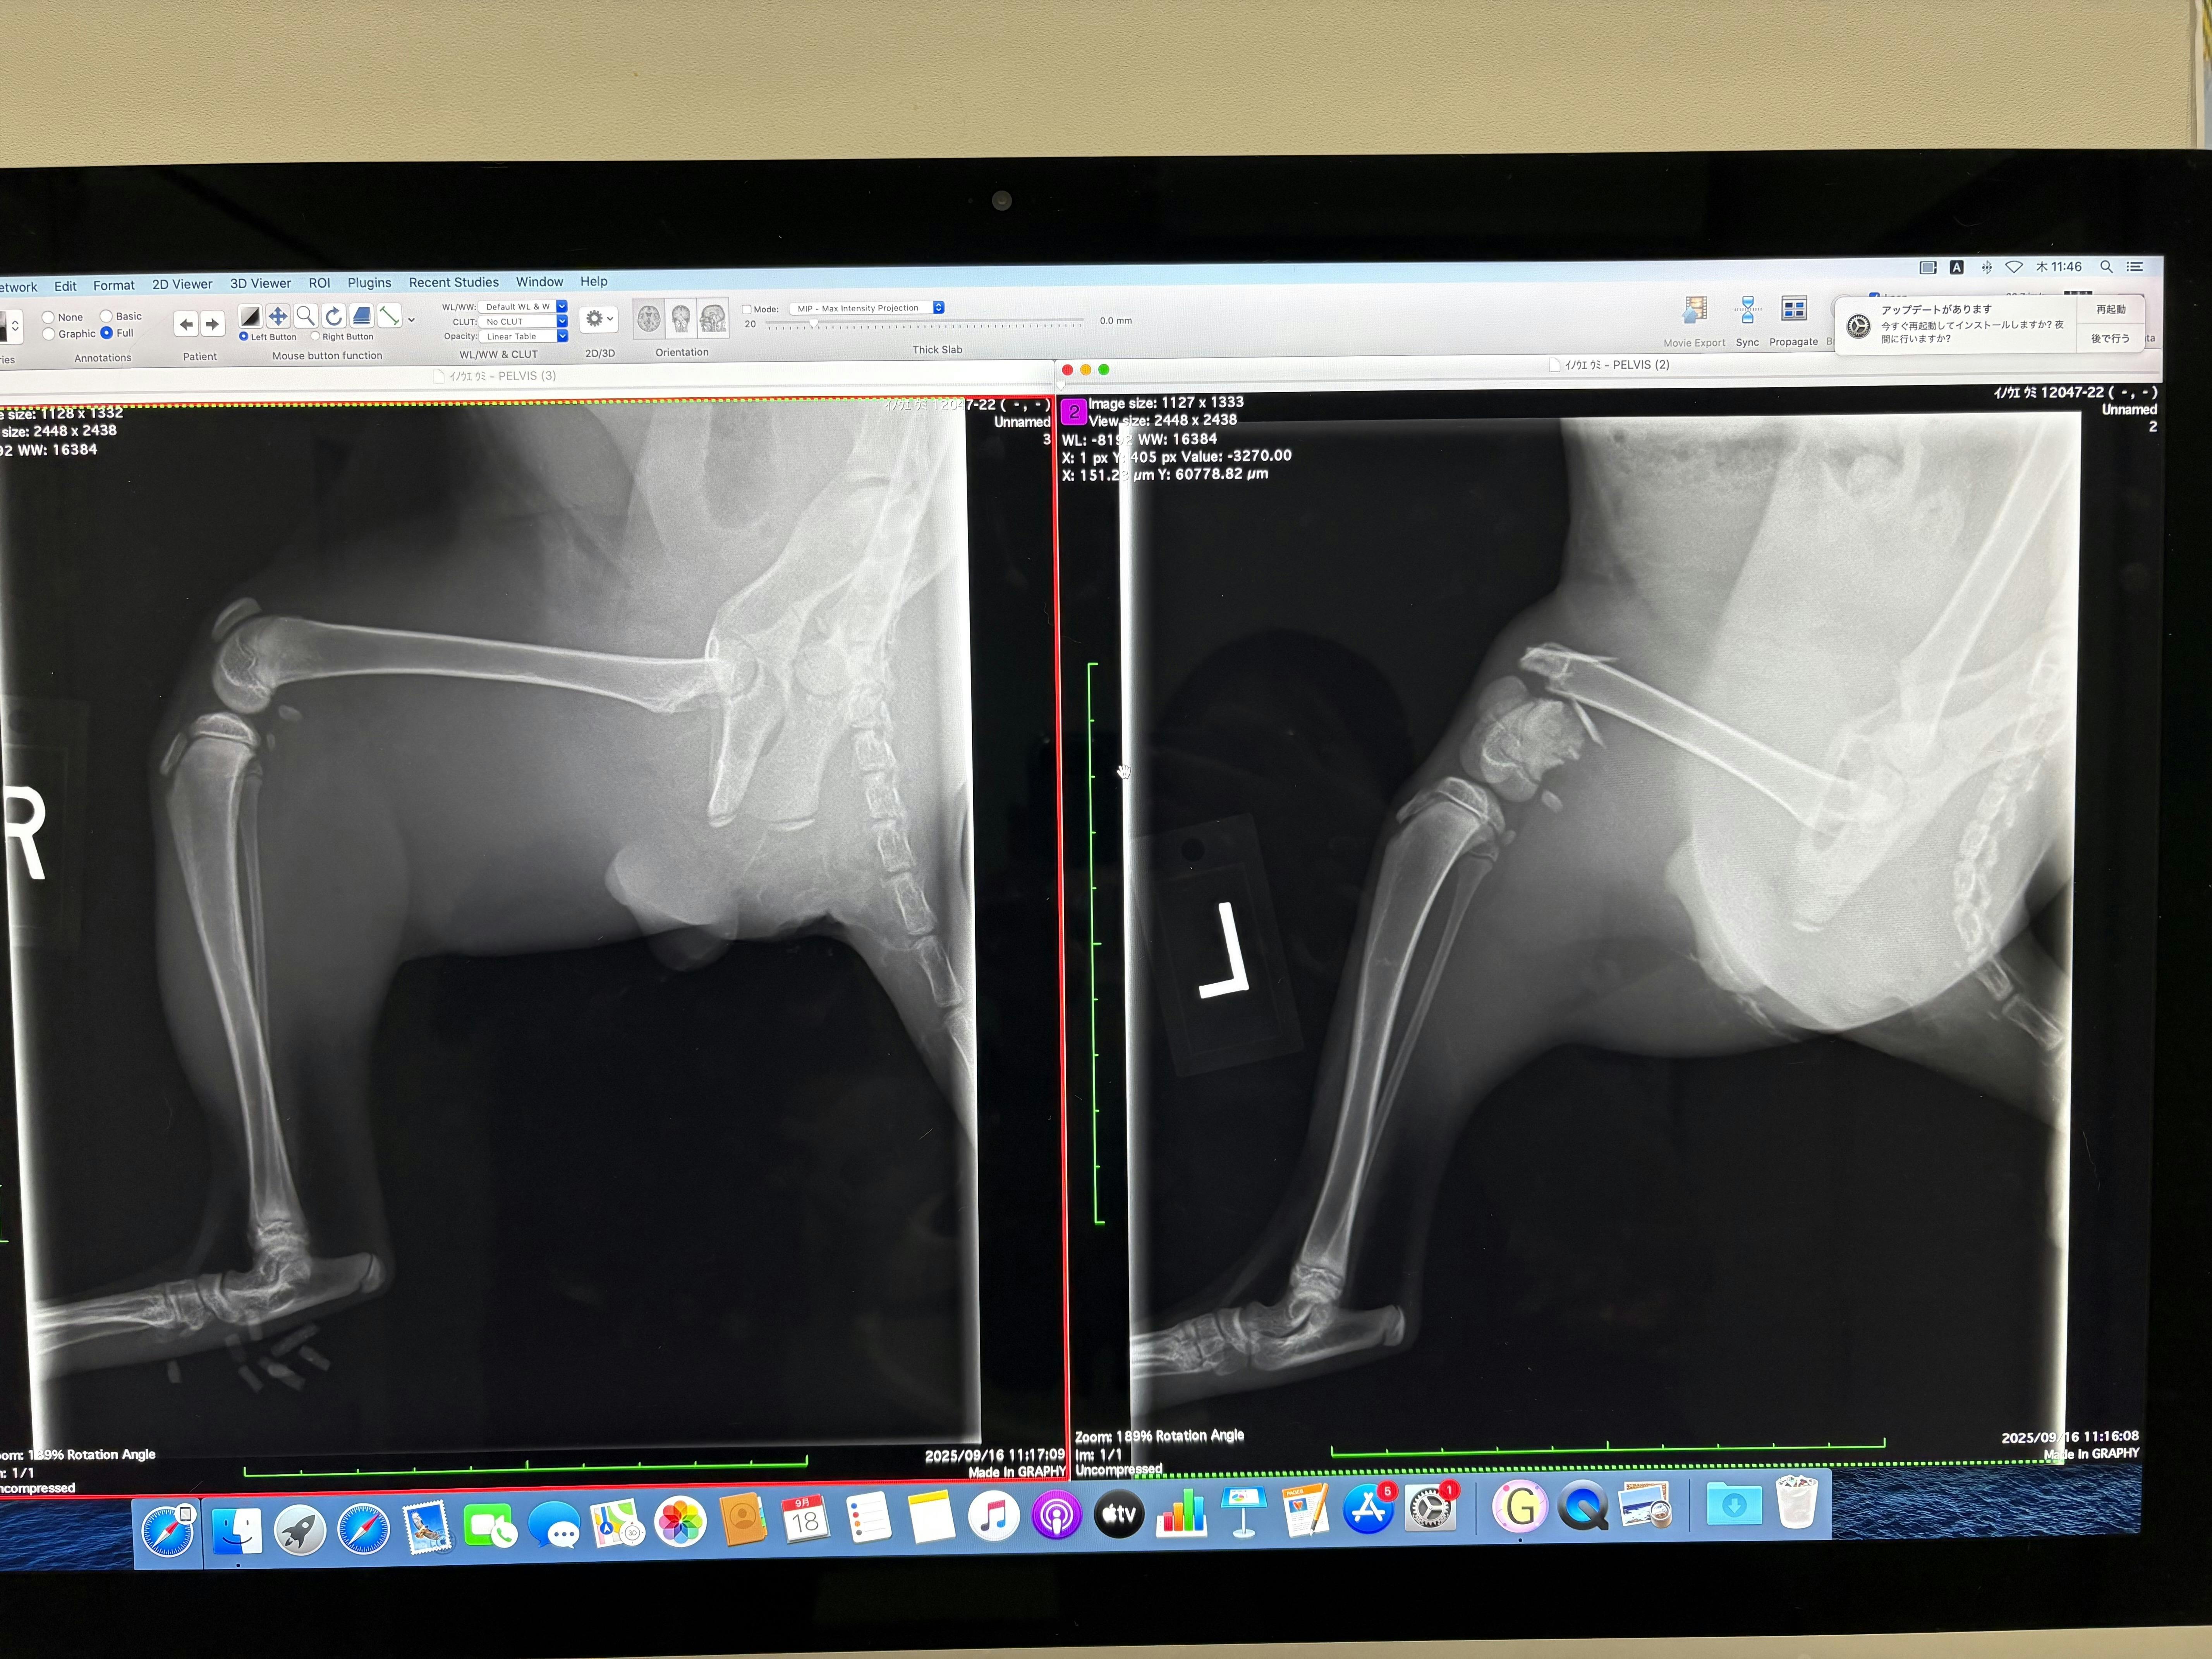

左が正常な骨 右が折れてる骨です

膝のところが折れてしまっています

折れてしまった部分にXのように交差してピンを入れる手術です

リスクとしては膝の部分がとても血が出やすく、貧血の可能性があると言うこととまだまだ子猫の小さい身体なので骨が小さく、ピンが骨からはみ出してしまうことでした。